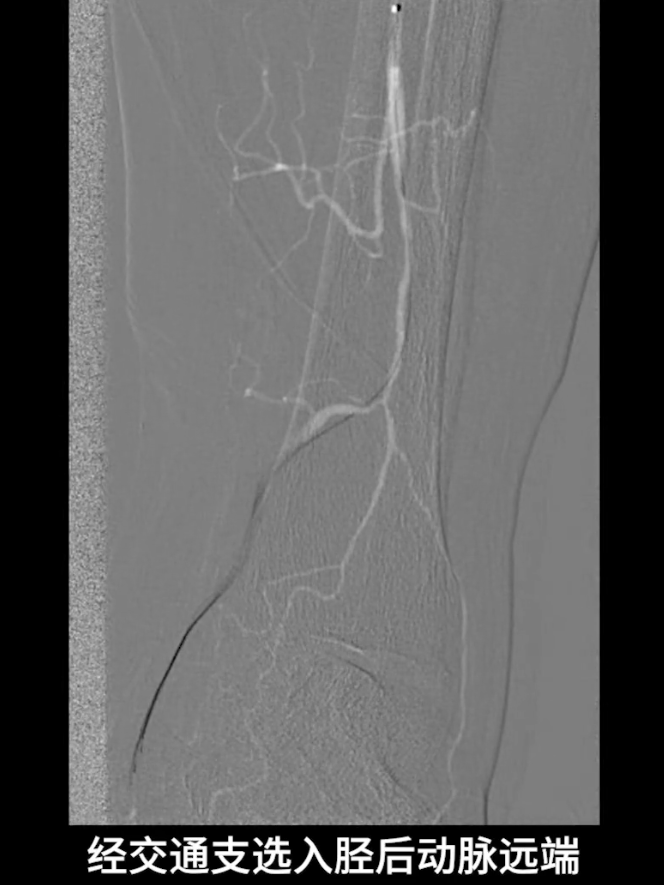

更换0.014系统导丝,经交通支选入胫后动脉远端,

再以2.0×40mm球囊扩张残余狭窄,并压迫远端逆行穿刺点止血,确保膝下流出道通畅。